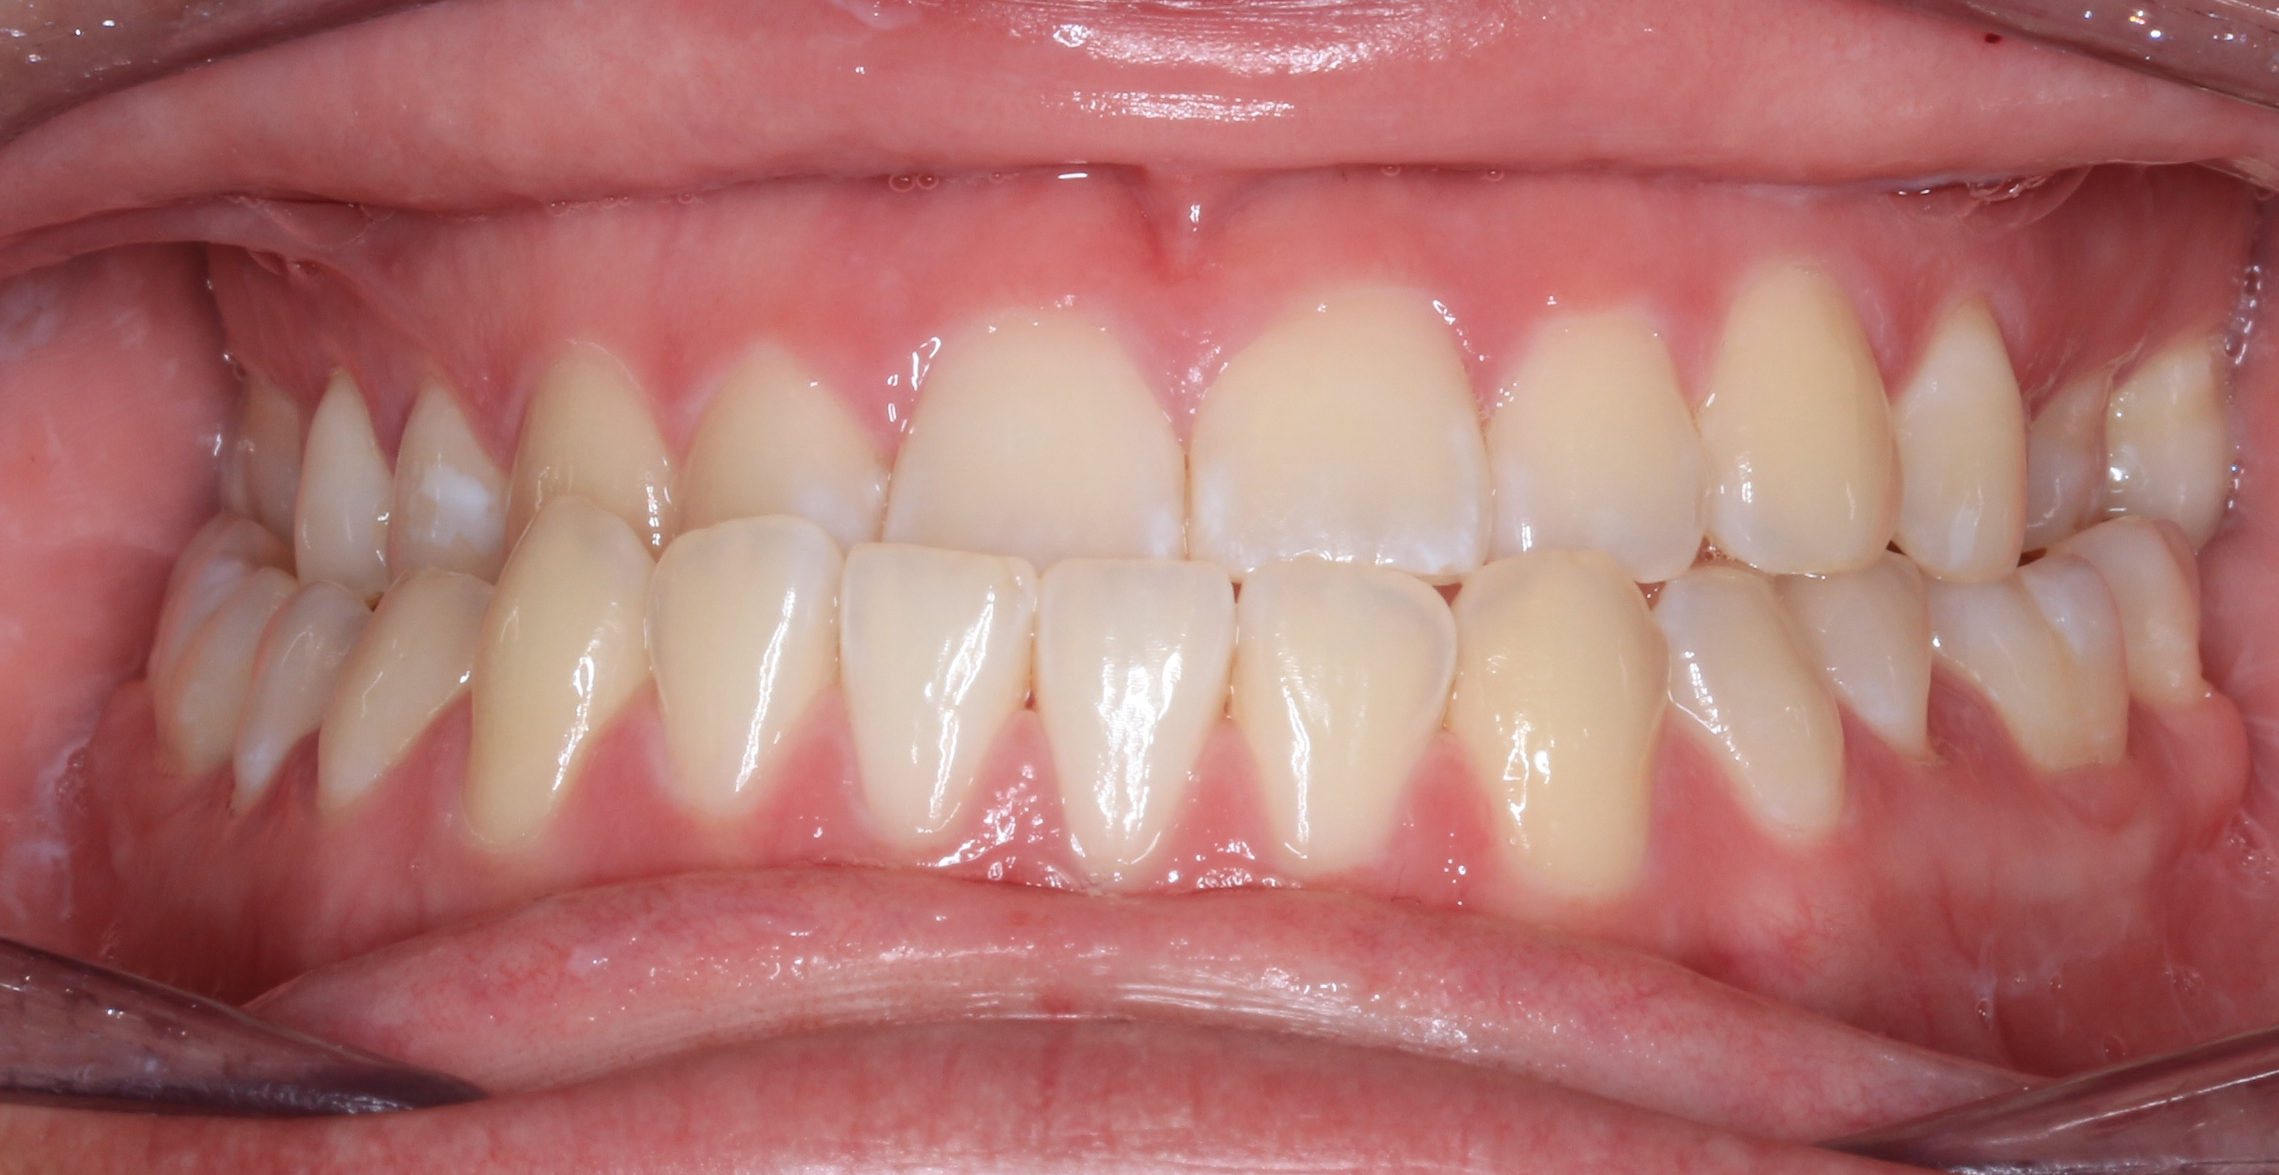

Before teeth alignment comparison: Intraoral before photo of Metal Self-Ligating Braces & Orthognathic Surgery showing the intraoral records reveal the magnitude of this correction. Before

This case began with a severe skeletal imbalance that braces alone could not correct. The patient presented with a significant Class III bite, asymmetric mandibular prognathism, anterior crossbite, and midline deviation. Because the jaw relationship was the root of the problem, a combined orthodontic and surgical approach was required to achieve the best stable, long-term result.

This transformation was designed with intention. Dr. Benson used braces to sculpt alignment and prepare the bite, then collaborated with an oral surgeon to reposition the mandible through orthognathic surgery. The result: a stable bite, restored facial balance, and symmetry achieved.